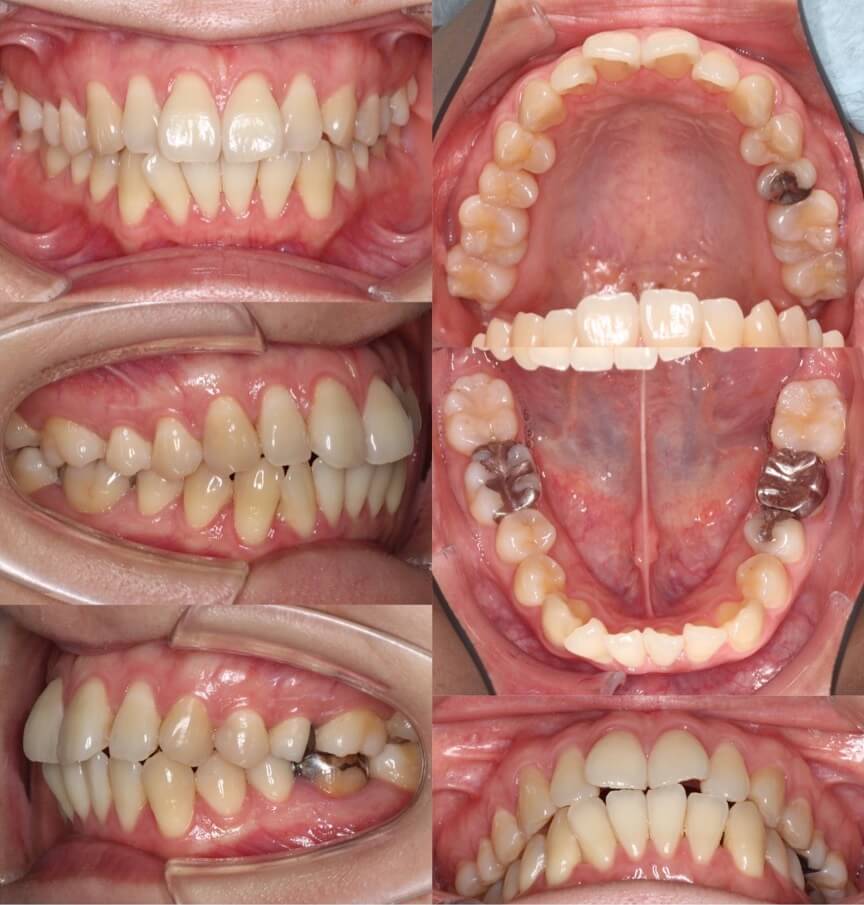

「前歯の角度が変化」

20代女性・ハーフリンガル装置・下あご後退型

前歯が前に傾斜している(倒れている)上下顎前突症例です。抜歯スペースに前歯を押し込むだけで、口元の突出が改善できる割と単純なケースになります。治療後は上下の前歯の角度も内向きに変わりました。

<症例概要>

主訴:前歯を引っ込めたい

年齢・性別:20代女性

住まい:千葉県佐倉市

症状:下顎後退・上下顎前歯唇側傾斜

治療方針:抜歯空隙の閉鎖(最大固定)

治療装置:ハーフリンガル矯正装置(上のみ裏側装置)

固定:歯科矯正用アンカースクリュー(口蓋側壁x2)

抜歯:上下第一小臼歯

治療期間:1年10か月

リテーナー:上下プレートタイプ+クリアタタイプ+フィックスタイプ

治療費用:1,4950,000(税込)

代表的副作用:痛み・治療後の後戻り・歯根吸収・歯髄壊死・歯肉退縮

▶︎その他の副作用